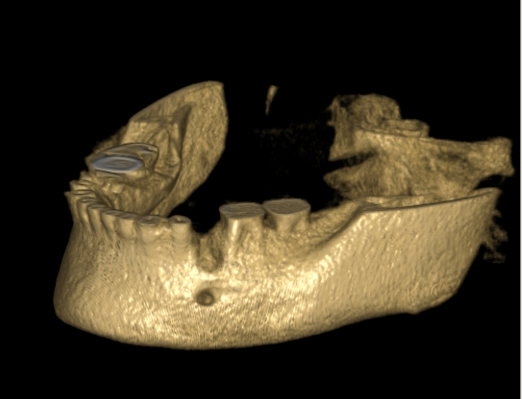

Tyto postupy nám umožní doplnit chybějící množství kosti v čelistech pacienta i zlepšit kvalitu kosti. Většinou se setkáváme s omezenou nabídkou kostní tkáně díky resorpčním (úbytkovým) procesům způsobených věkem či vytržením zubu, přítomností anatomických struktur jako je čelistní dutina, nervový kanál nebo patologických či poúrazových stavů - cysty, zlomeniny.

Při ztrátě molárů a premolárů v horní čelisti a jejich náhradě implantáty se často setkáváme s nedostatečnou vertikální nabídkou kosti pod čelistní dutinou, často doprovázenou i nedostatečnou horizontální nabídkou a sníženou kvalitou kosti

(v oblasti 2. premoláru v 50%, v oblasti moláru až v 80% případů nedostatečná kostní nabídka)

Jedná se o vyzvednutí membrány, která čelistní dutinu vystýlá, pod vyzvednutou membránou vznikne kapsa, kam se umístí augmentační materiál, do kterého se zavedou implantáty.